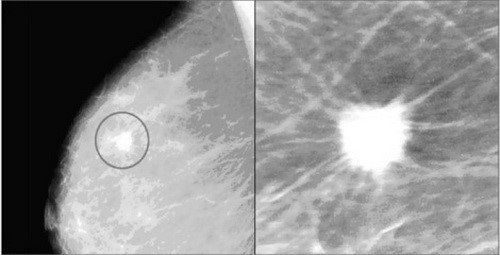

X-quang vú được sử dụng để phát hiện các bất thường về vú, đây không phải phương tiện để có tiêu chuẩn vàng trong chẩn đoán ung thư, tuy nhiên dựa vào phương tiện này, bác sỹ phát hiện được vị trí nghi ngờ và chỉ định các can thiệp cần thiết lấy mô bệnh phẩm để xét nghiệm nếu cần thiết. Hai triệu chứng điển hình hay thấy trên phim X-quang vú là vôi hóa và các khối.

Khối: khối là vùng xuất hiện tăng đậm độ quang trên phim X-quang vú, có hình dạng và bờ viền khác so với nhu mô vú. Kèm theo hoặc không kèm theo vi vôi hóa, bờ viền và hình dạng của khối cần được đánh giá cẩn thận dấu hiệu của ung thư. Khối thấy trên phim X-quang vú có thể là nang hoặc các khối đặc. Thông thường, phối hợp với siêu âm sẽ giúp cho bác sĩ có thêm thông tin để chẩn đoán về khối phát hiện trên X-quang vú.

- BIRADS 4: Tổn thương nghi ngờ ác tính (từ 2-95% ác tính), bạn cần phải được sinh thiết để chẩn đoán xác định.

- BIRADS 5: Tổn thương nghi ngờ ác tính cao (> 95% ác tính), bạn chắc chắn cần phải được sinh thiết sớm để chẩn đoán xác định.